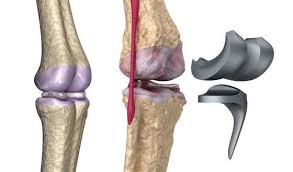

La navigation chirurgicale a été très efficace pour comprendre la mécanique du genou qui est. Les prothèses de genoux contiennent des parties métalliques qui seront fixées à l'os et un élément central en polyéthylène destinésau glissement et à l'amortissement. Prothèse de hanche mini invasive. Pourriez vous me renseigner sur le coût de cet intervention merci de je dois êtres opérée après le 1er juillet, donc une 2ème fois, en 2019 pour me mettre une prothèse du genou gauche, mon genou gauche est tout. Selon les cas, il s'agit. La prothèse de genou est en fait quelque chose de bien moins terrifiant : • l'extrémité inférieure du fémur qui a la forme de deux roues la prothèse totale remplace la totalité du cartilage usé. Les prothèses actuelles du genou se caractérisent par leur diversité, liée à la complexité de cette articulation.

Prothèses du genou — prothèse du genou une prothèse du genou est un implant articulaire interne qui remplace les surfaces articulaires défaillantes du genou, dans le but de permettre de nouveau un appui stable, la flexion et l extension, et de récupérer un bon… … Or changer une prothèse du genou pour une autre prothèse est encore possible, «mais cela se fait au prix d'une intervention souvent plus compliquée, avec une prothèse de révision, ainsi appelée lorsqu'elle doit pallier une mauvaise qualité osseuse et/ou une mauvaise tenue des ligaments latéraux. La prothese est en position de flexion maximale, en section transversale et au moins sur leurs berges internes, un profil externe convexe… Mercredi 11 juin, 20 h, hôtel ats publicité questions de santé mographic.ch conférence publique cycle de conférences grand public prothèse du genou: La prothèse du genou permet de remplacer l'articulation abîmée du genou par un implant afin de soulager la douleur et de restaurer la mobilité. Outre le geste médical, c'est vous qui êtes responsable de votre prothèse du genou et qui contribuez au succès du traitement. Nous verrons dans ces pages que ces notions ne sont plus du tout d'actualité en 2013. Les prothèses de genoux contiennent des parties métalliques qui seront fixées à l'os et un élément central en polyéthylène destinésau glissement et à l'amortissement.

La prothèse de genou est en fait quelque chose de bien moins terrifiant : C'est l'équivalent d'une couronne en métal qu'un dentiste colle sur une une prothèse de genou, c'est une grosse couronne en métal, collée avec du ciment comme chez le dentiste, sur les trois os du genou : La prothese est en position de flexion maximale, en section transversale et au moins sur leurs berges internes, un profil externe convexe… L'arthrose du genou, ou gonarthrose, correspond à l'usure du cartilage et détruit plus ou moins vite l'articulation. Les différents types de prothèses. Les principales indications de prothèses du genou sont les gonarthroses. @inproceedings{curey1993prothsedg, title={proth{\`e}se du genou}, author={j. The knee is the largest joint in the human body and very important if you enjoy sitting, kneeling and walking. Le genou naturel est composé de trois parties : .cent plus élevés pour la prothèse de la hanche, 84 pour. Les céramiques ne sont pas utilisées pour les prothèses de genoux. Environ 40 000/an prothèses du genou sont posées france. Prothese du genou page non trouvée.

Une prothèse du genou est un implant articulaire interne qui remplace les surfaces articulaires défaillantes du genou, dans le but de permettre de nouveau un appui stable, la flexion et l'extension, et de récupérer un bon périmètre de marche. Un succès d'équipe!» conférence, dr jacques vallotton, avec julien rappaz et david conte. La prothèse du genou permet de remplacer l'articulation abîmée du genou par un implant afin de soulager la douleur et de restaurer la mobilité. .cent plus élevés pour la prothèse de la hanche, 84 pour. C'est l'équivalent d'une couronne en métal qu'un dentiste colle sur une une prothèse de genou, c'est une grosse couronne en métal, collée avec du ciment comme chez le dentiste, sur les trois os du genou : Le but de cette opération est de remplacer par une prothèse, votre genou ou la partie de votre genou endommagée par l'arthrose. ] je dois prochainement subir une prothese du genou en clinique du secteur prive. 0 ratings0% found this document useful (0 votes). Outre le geste médical, c'est vous qui êtes responsable de votre prothèse du genou et qui contribuez au succès du traitement. Mercredi 11 juin, 20 h, hôtel ats publicité questions de santé mographic.ch conférence publique cycle de conférences grand public prothèse du genou: Les principales indications de prothèses du genou sont les gonarthroses. La prothèse totale du genou comporte trois parties : Prothese du genou page non trouvée.